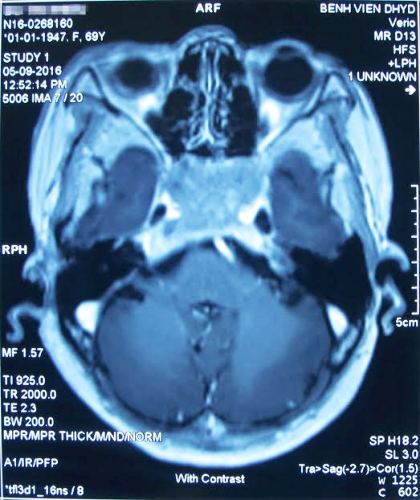

Thạc sĩ, bác sĩ Trương Thanh Tình, Khoa Ngoại Thần Kinh, chỉ định bệnh nhân chụp MRI xác định có u não vùng sàn sọ đường giữa ngoài màng cứng. Khối u nhiều mạch máu, kích thước lớn, gây hủy xương bản vuông và xâm lấn nhiều cấu trúc xung quanh như xoang hang, động mạch cảnh 2 bên. Bà Nguyệt được xác định mắc bệnh lý hiếm gặp của u sàn sọ là Clival chordoma, hay u nguyên sống. Đây chính là nguyên nhân gây đau đầu, mệt mỏi, mờ mắt...

Khối u sàn sọ kích thước lớn (màu trắng ở giữa) đã xâm lấn nhiều cấu trúc xung quanh như xoang hang, động mạch cảnh 2 bên.